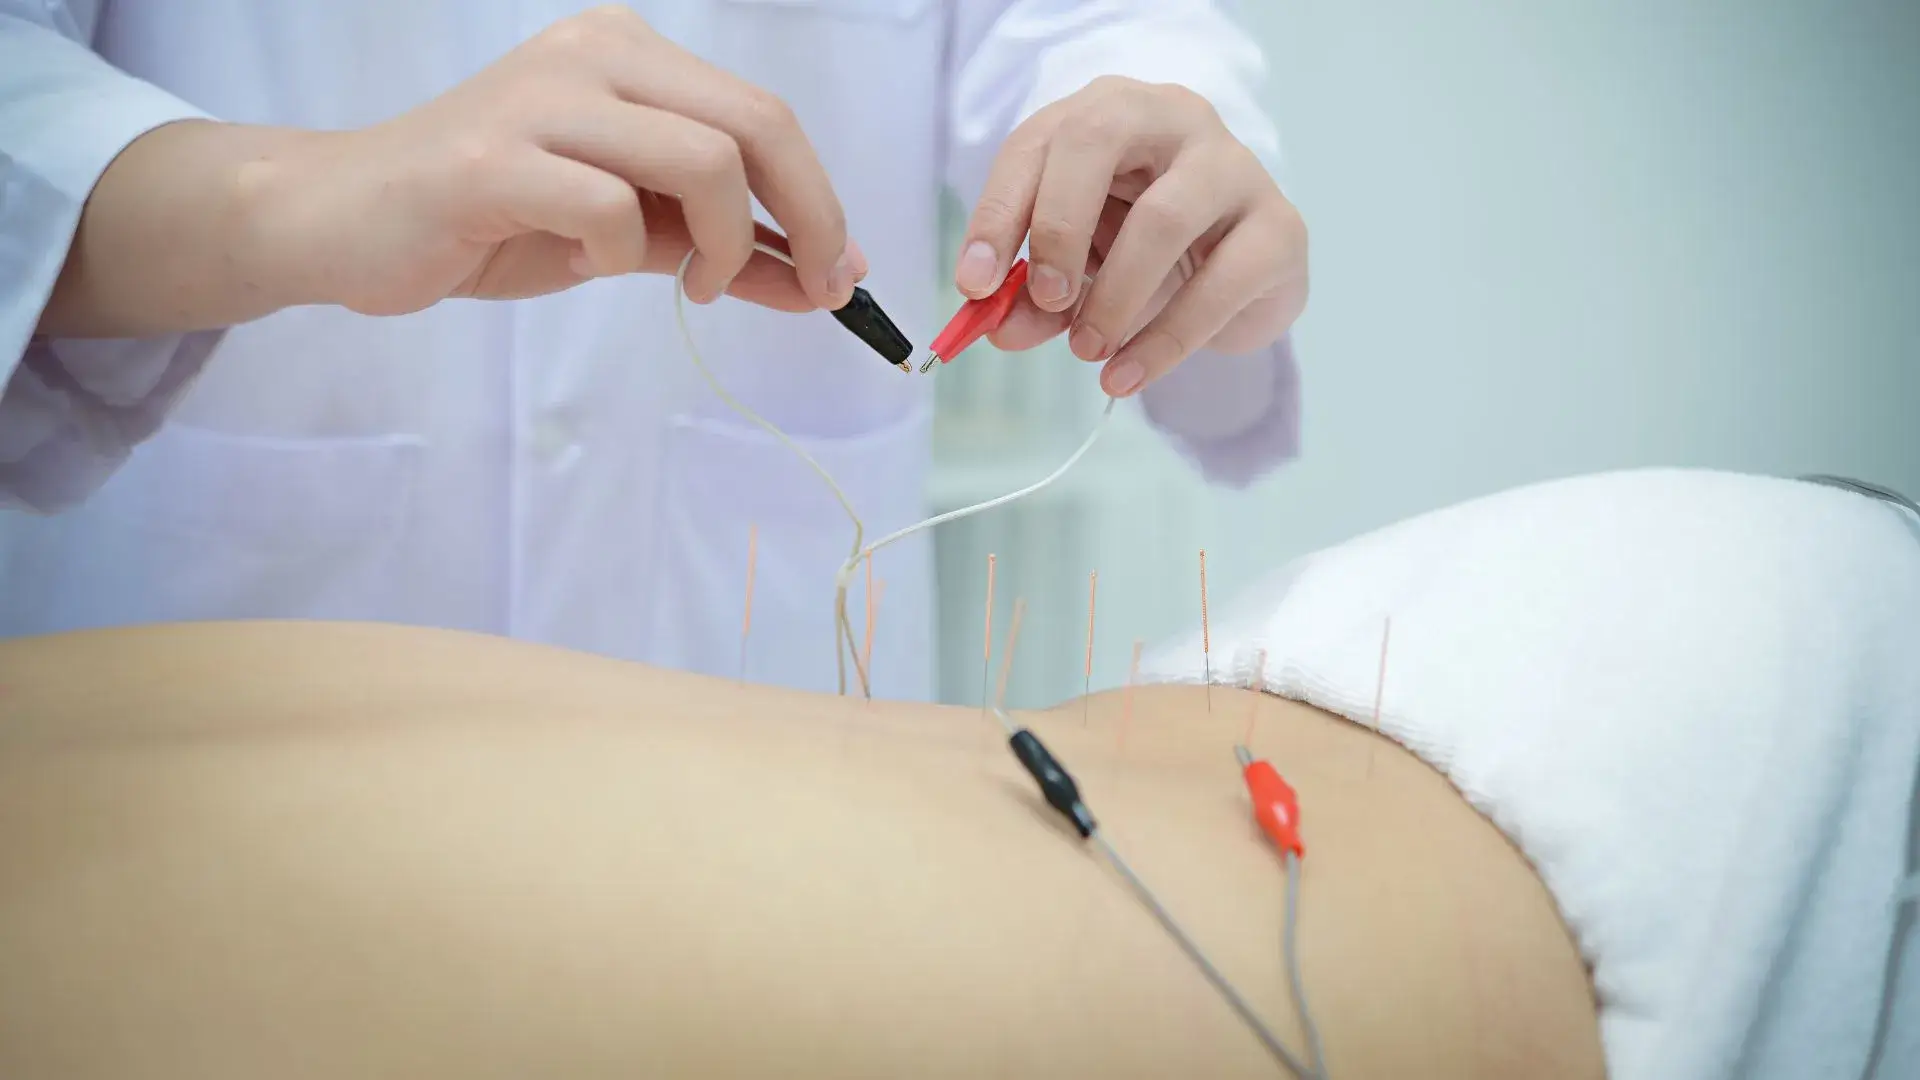

Georgetown Acupuncture at Natural Health Clinic of Halton (in the vicinity of the New Georgetown Trafalgar Memorial Hospital) are all professionally trained. We thoroughly assess each patient’s case and create a specific individualized wellness treatment plan to attain overall balance in the body. Georgetown Acupuncturists, (905) 582-2360 Acupuncture, an Ancient Treatment for a Current Problem. Acupuncture is known to treat a variety of conditions, s...

Cosmetic Acupuncture is an effective and non-invasive treatment to reduce the signs of aging. The treatment involves insertion of very fine and sterile needles on key points and areas on the face. Acupuncture improves the circulation of qi and blood on the face. These needles also stimulate collagen production improving the elasticity of the facial muscle and making it look firmer.